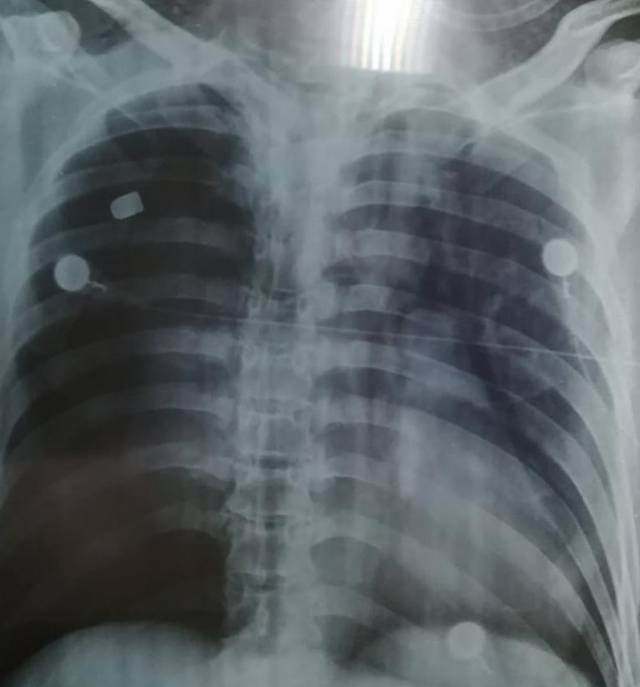

De acuerdo con la versión de testigos, los jóvenes tuvieron una riña y derivado de esta pelea fueron agredidos con un arma de fuego, recibiendo en ambos casos disparos en la zona del tórax, por lo que su situación de salud es delicada en ambos casos.

Tras haber sido lesionados, uno de ellos fue trasladado al Hospital privado San Martín de Porres ubicado en la ciudad rielera y el otro fue llevado de urgencia al Hospital Regional de Tzompantepec, en donde buscan salvarle la vida.